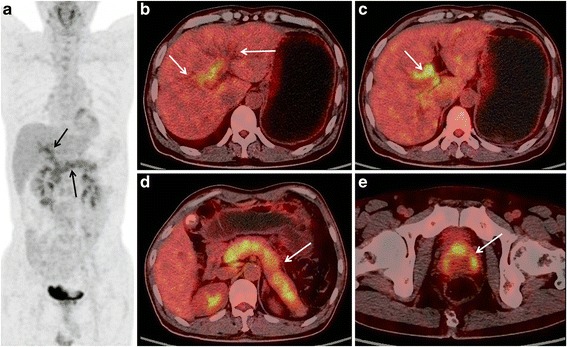

Fig. 1.

A 55-years old male patient with AIP. The MIP PET image (a) shows a diffuse and heterogeneous increase of FDG uptake in the pancreas, as well as increased FDG activity along the bile duct; PET/CT fusion images (b) depicts bile duct dilatation; (c), increased FDG activity of the hilar bile duct is shown; (d) shows diffusely enlarged pancreas with capsule-liked rim and a heterogeneous increase of FDG uptake. e, there is an inverted “V” shaped high FDG uptake in the prostate